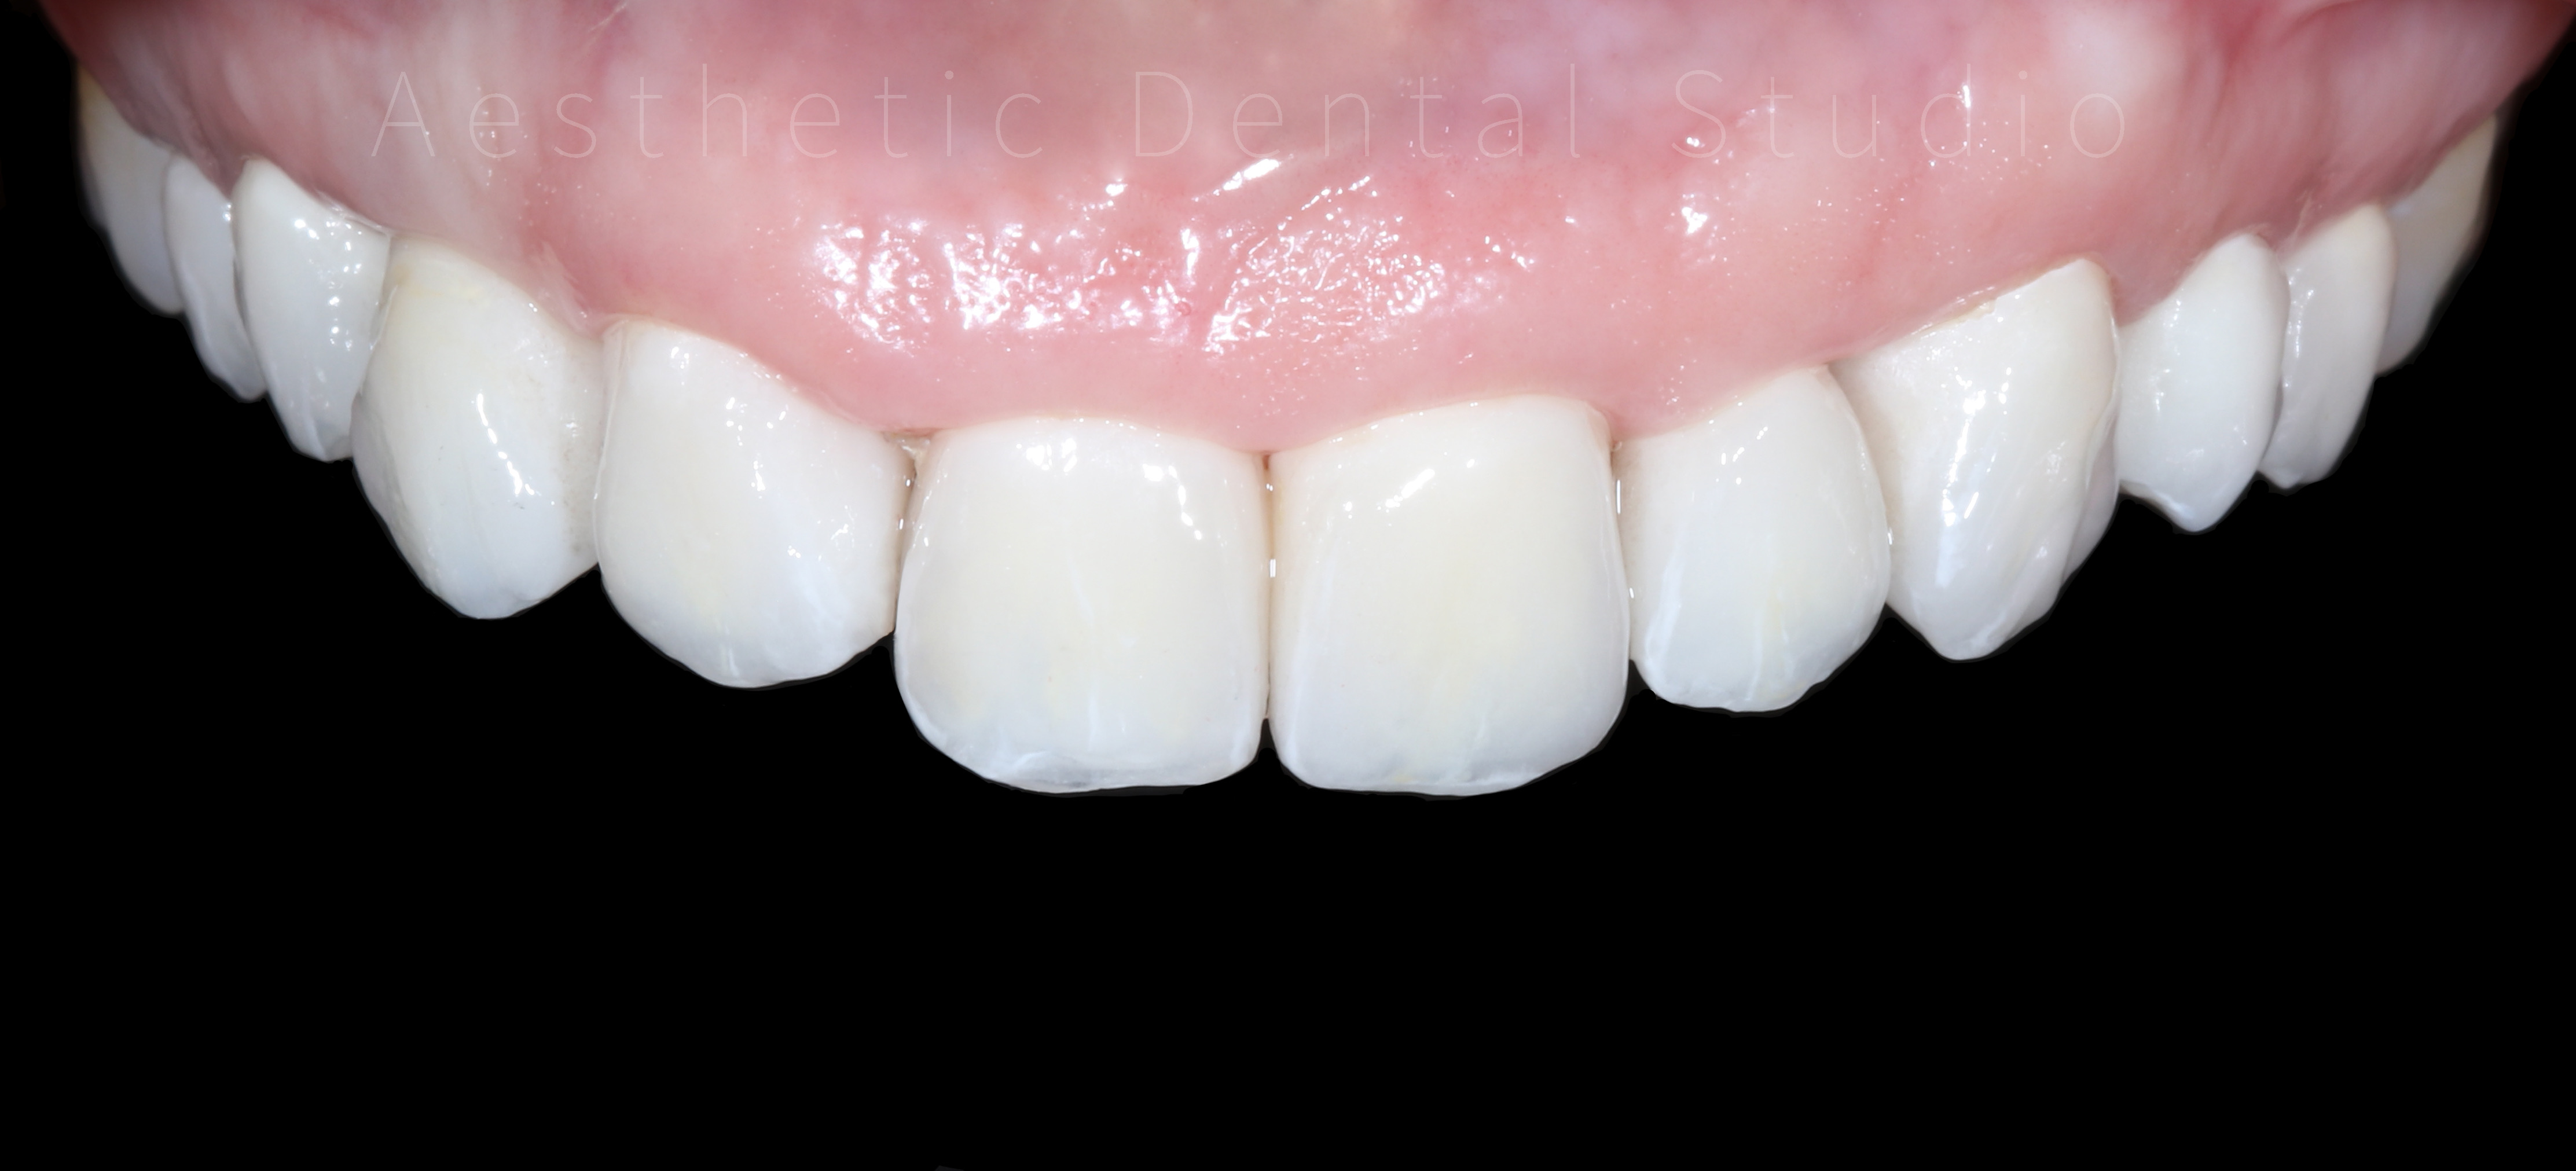

Ακολούθησε η προετοιμασία των δοντιών και η λήψη ψηφιακών αποτυπωμάτων με ενδοστοματικό σαρωτή, τα οποία στάλθηκαν στο συνεργαζόμενο εργαστήριο. Εκεί σχεδιάστηκαν και κατασκευάστηκαν ολοκεραμικές αποκαταστάσεις υψηλής αισθητικής, με απόλυτη ακρίβεια εφαρμογής και χρωματική φυσικότητα. Οι τελικές όψεις και στεφάνες τοποθετήθηκαν στα δόντια της ασθενούς μετά από προσεκτικό έλεγχο αισθητικής, φώνησης και λειτουργίας, επιτυγχάνοντας απόλυτη εναρμόνιση με το πρόσωπο.

Τελικό αποτέλεσμα

Το τελικό χαμόγελο ήταν φυσικό, φωτεινό και αρμονικό, αναδεικνύοντας τα χαρακτηριστικά της ασθενούς, χωρίς υπερβολές. Η θεραπεία ολοκληρώθηκε μέσα σε 10 ημέρες, συνδυάζοντας αισθητική αριστεία, λειτουργική σταθερότητα και άριστο χρονοπρογραμματισμό. Η ασθενής αναχώρησε από την Καλαμάτα με ένα εντελώς ανανεωμένο χαμόγελο, απολαμβάνοντας τη μοναδική εμπειρία ενός αισθητικού ταξιδιού οδοντιατρικής φροντίδας στην Ελλάδα